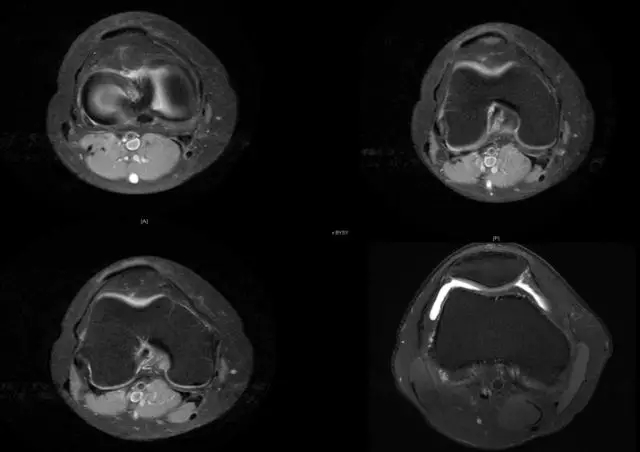

segond骨折

外髁骨擦伤(Kissing -sign)

陈旧性前交叉韧带断裂